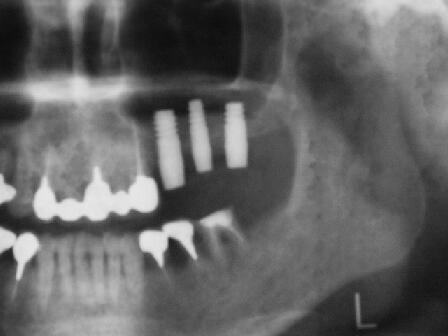

インプラント埋入2ヵ月後のエックス線写真と口腔内写真

インプラント体(フィクスチャー)の周りに骨が出来始めている

4ヵ月後のエックス線写真

4ヶ月して、当初1~3ミリしか存在しなっかた骨が7~12ミリ程度(部位によって違う)になる